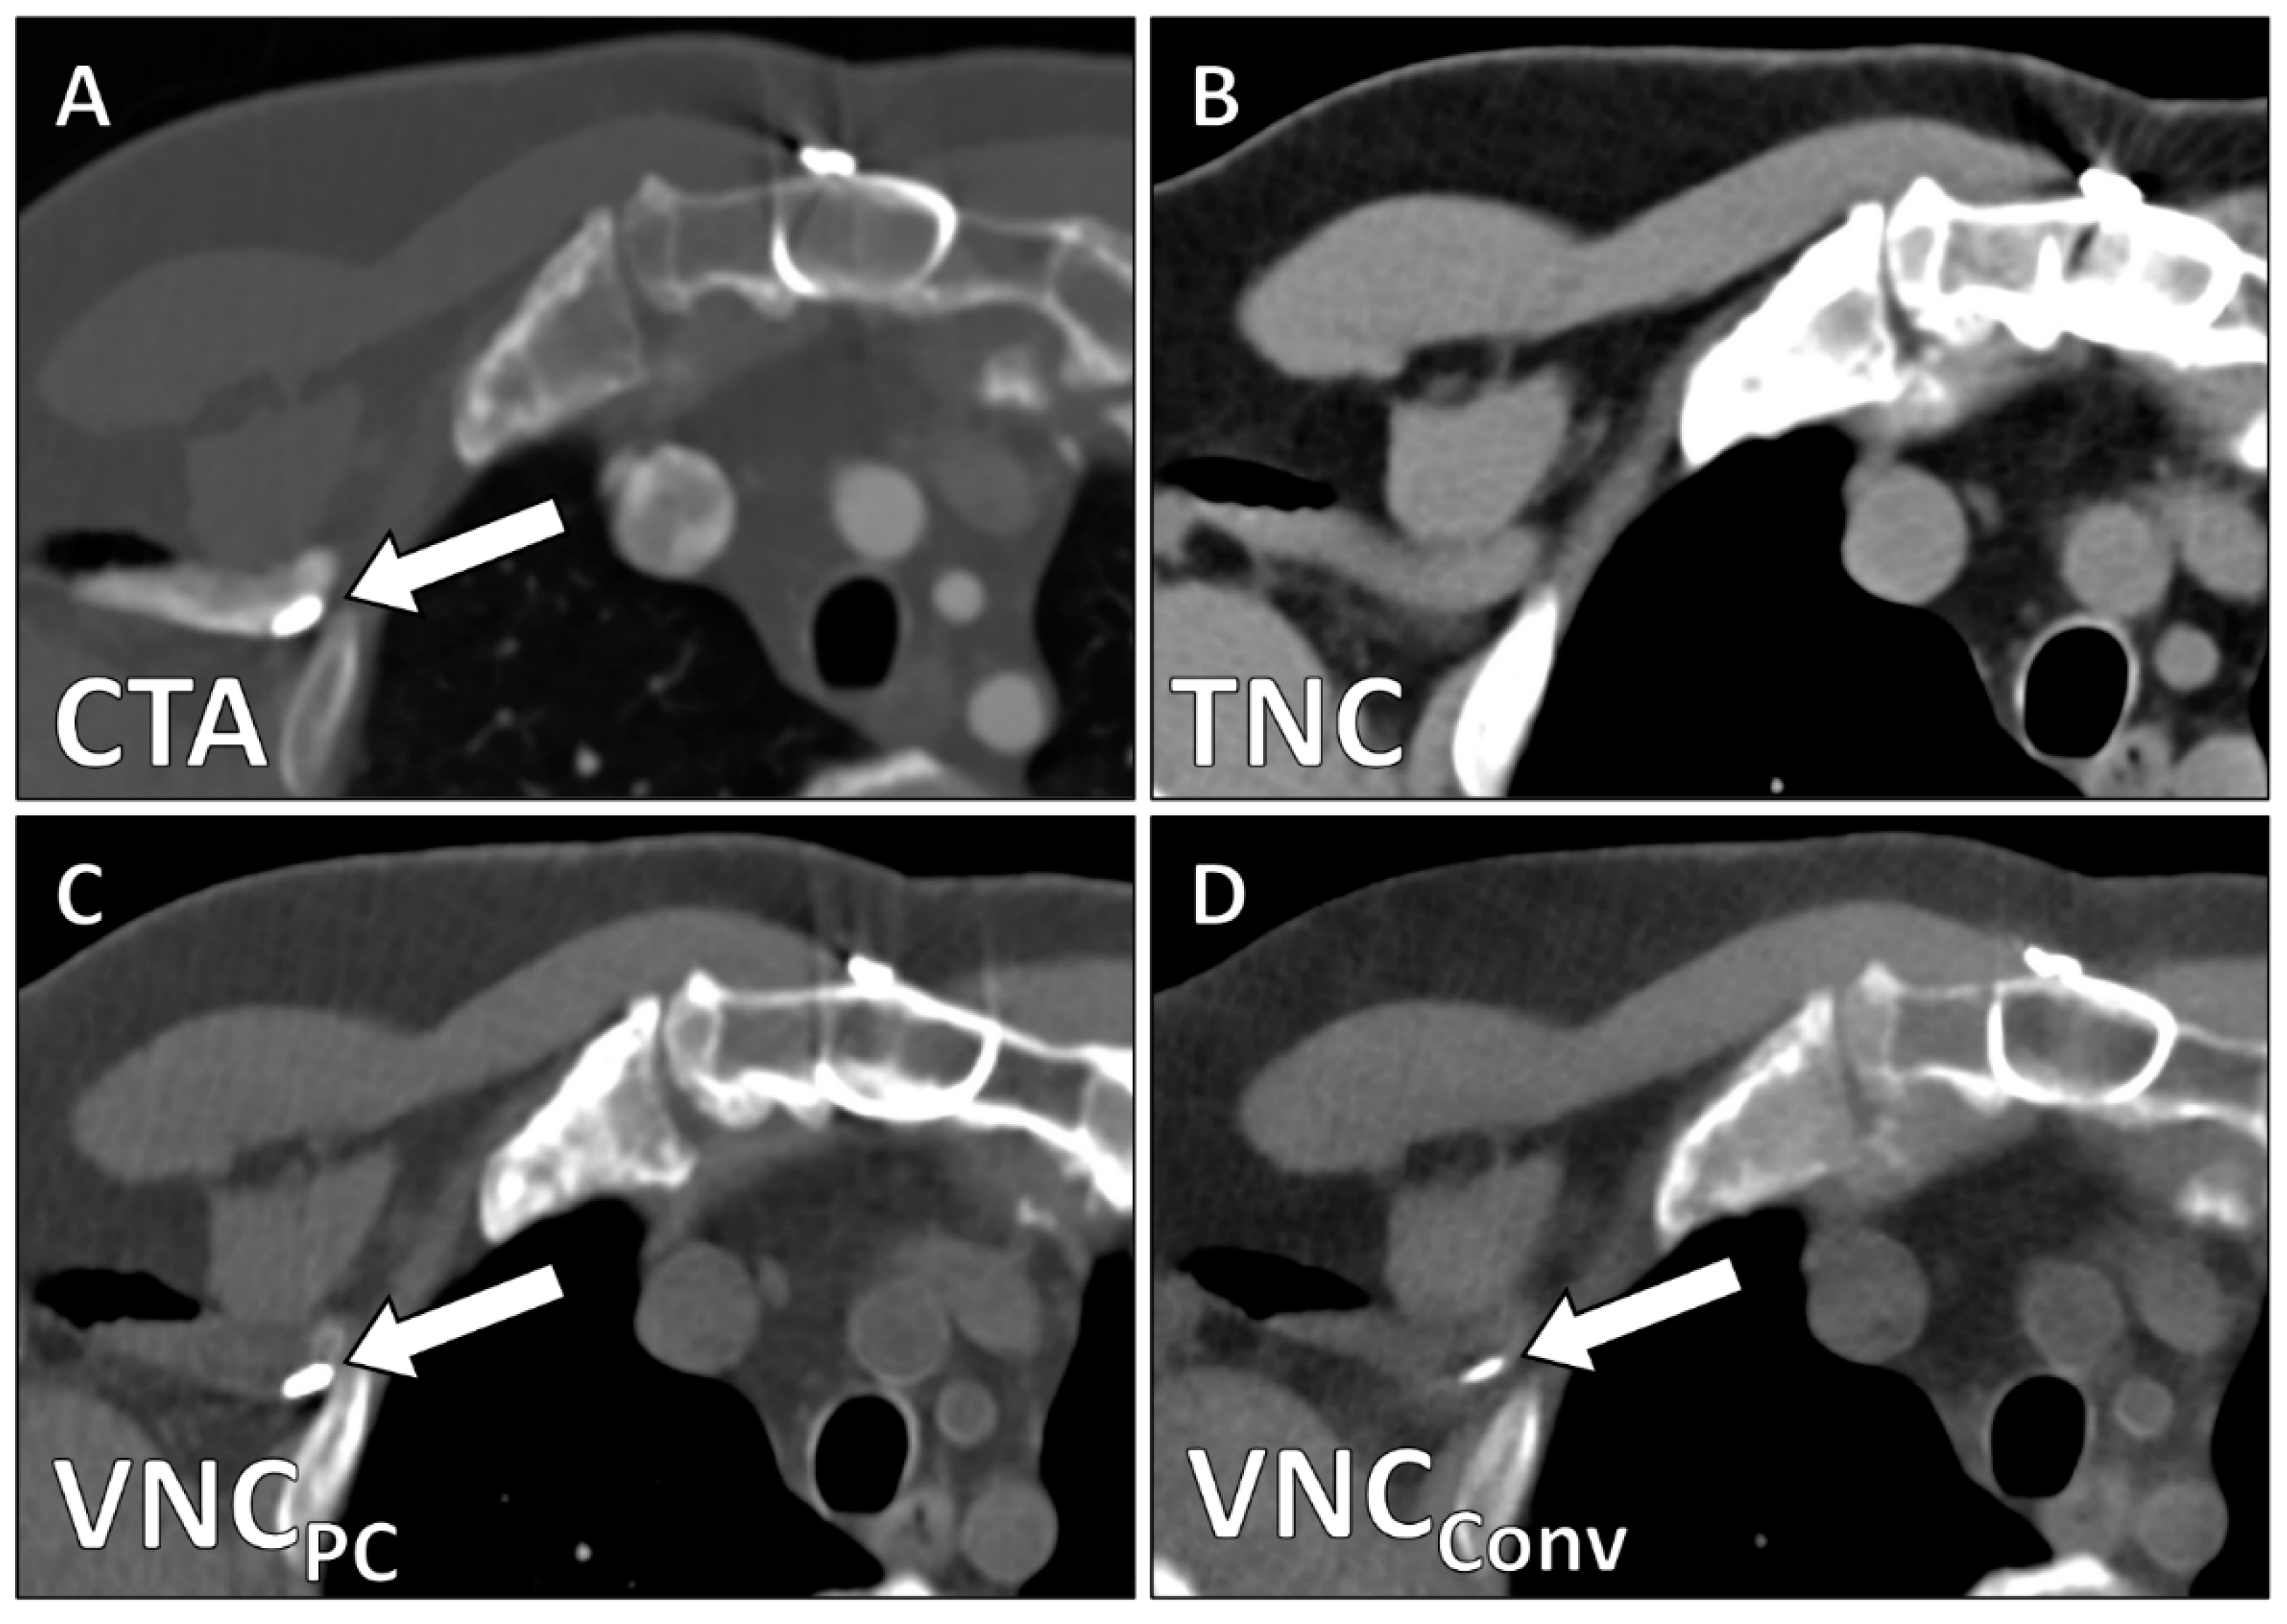

| Image Quality | 4.2 ± 0.9 | 0.68 (0.44–0.78) | 2.5 ± 0.6 | 0.62 (0.43–0.77) | <0.001 |

| Calcium Subtraction | 4.6 ± 0.5 | 0.75 (0.66–0.82) | 3.0 ± 0.6 | 0.58 (0.40–0.71) | <0.001 |

| Stent Subtraction | 4.7 ± 0.7 | 0.72 (0.58–0.81) | 3.8 ± 1.2 | 0.62 (0.49–0.77) | 0.003 |